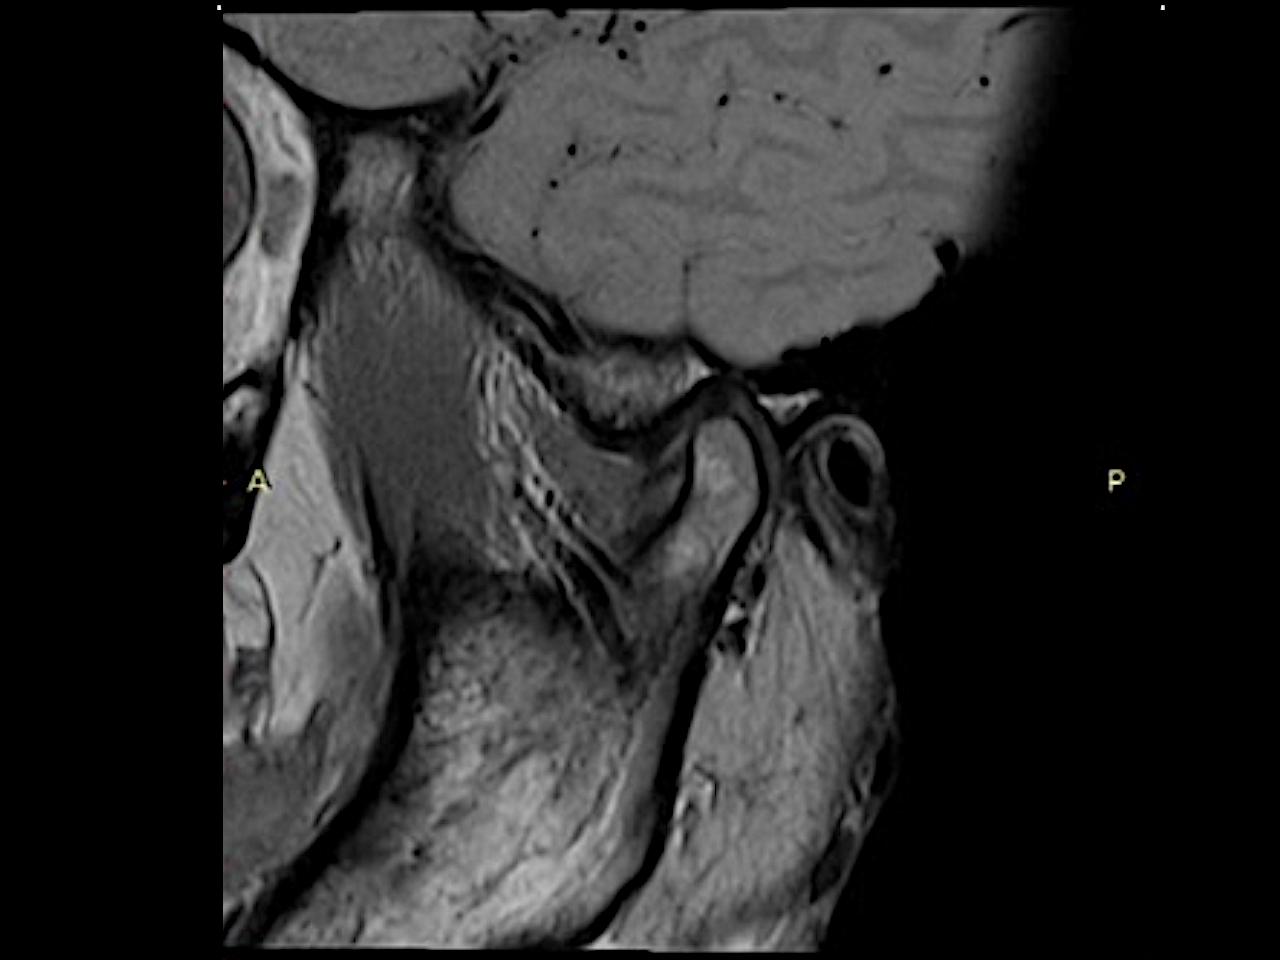

From mrimaster.com

Temporomandibular Joint Anatomy MRI TMJs Anatomy Free Sagittal Tmj Joints Xray A panoramic radiograph is considered a “screening” projection and is often used in. the temporomandibular joint (tmj) is an atypical synovial joint located between the condylar process of the mandible and the mandibular fossa and. temporomandibular joint (tmj) dysfunction is characterized by an abnormal relationship between the disc and the adjacent articular. if your doctor or dentist. Tmj Joints Xray.